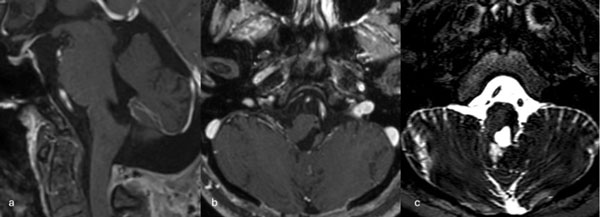

Figura 3. RM preoperatoria de encéfalo. Se evidencia una lesión única intraaxial centrada en puente y pedúnculo cerebeloso derecho, sugerente de un cavernoma roto. A, B y C) Imágenes ponderadas en T2 en cortes sagital, axial y coronal, respectivamente, donde se observa un importante hiperintensidad perilesional, sugerente de edema.

Figura 5. RM postquirúrgica de encéfalo. Se evidencia una exéresis completa con hiperintensidad en T2 en regresión. A, B y C) Imágenes ponderadas en T2 en cortes coronal, axial y sagital, respectivamente.